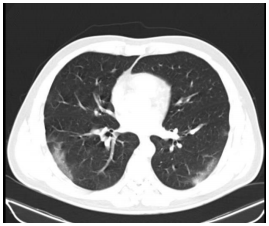

I. Pneumonia bacteriana. II. Pneumonia viral por influenza. III. Pneumonia organizante. IV. Pneumonia viral por covid-19.

Quais estão corretas?